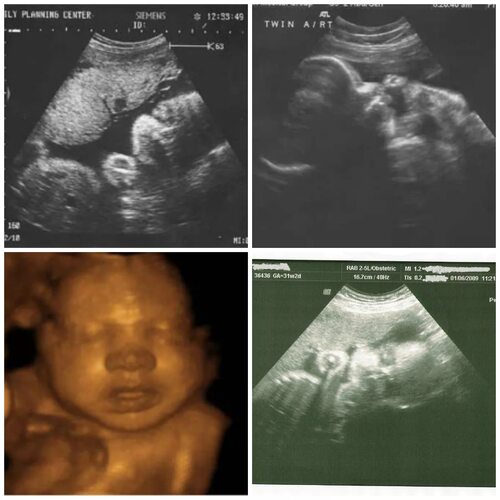

Ультразвуковое исследование (УЗИ) является одним из наиболее распространенных методов диагностики в медицине. Во время УЗИ врач использует специальный аппарат, называемый ультразвуковым сканером, чтобы создать изображение внутренних органов и тканей пациента.

УЗИ может использоваться для визуализации различных органов и систем в организме. Фото УЗИ могут включать изображения:

Фото УЗИ могут также показывать структуру и состояние тканей, опухоли или кисты, а также помогать в определении причин заболеваний или состояний пациента.

Для получения фото УЗИ пациенту обычно предлагается лечь на специальный стол в позиции, наиболее удобной для проведения исследования. Врач наносит гель на кожу в области, которую необходимо исследовать, и затем прокатывает ультразвуковую головку по поверхности кожи. Ультразвуковые волны проникают внутрь органов и тканей, отражаются от них и возвращаются обратно к ультразвуковой головке, где преобразуются в изображение на экране.

Фото УЗИ могут быть черно-белыми или цветными, в зависимости от настроек ультразвукового сканера. Они могут быть сохранены в цифровом формате для последующего анализа и диагностики.